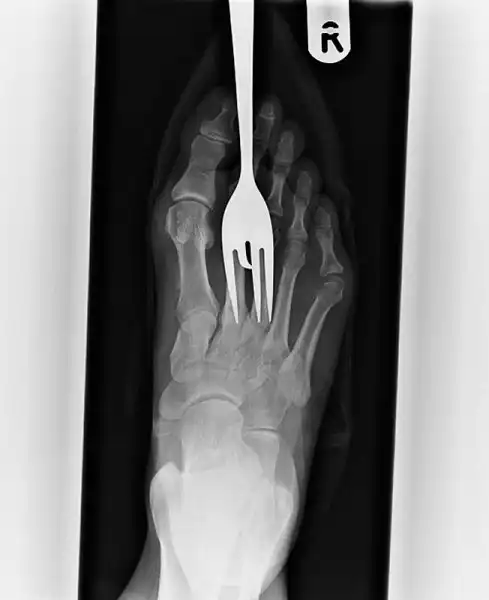

Еще один пациент, наступивший на вилку.